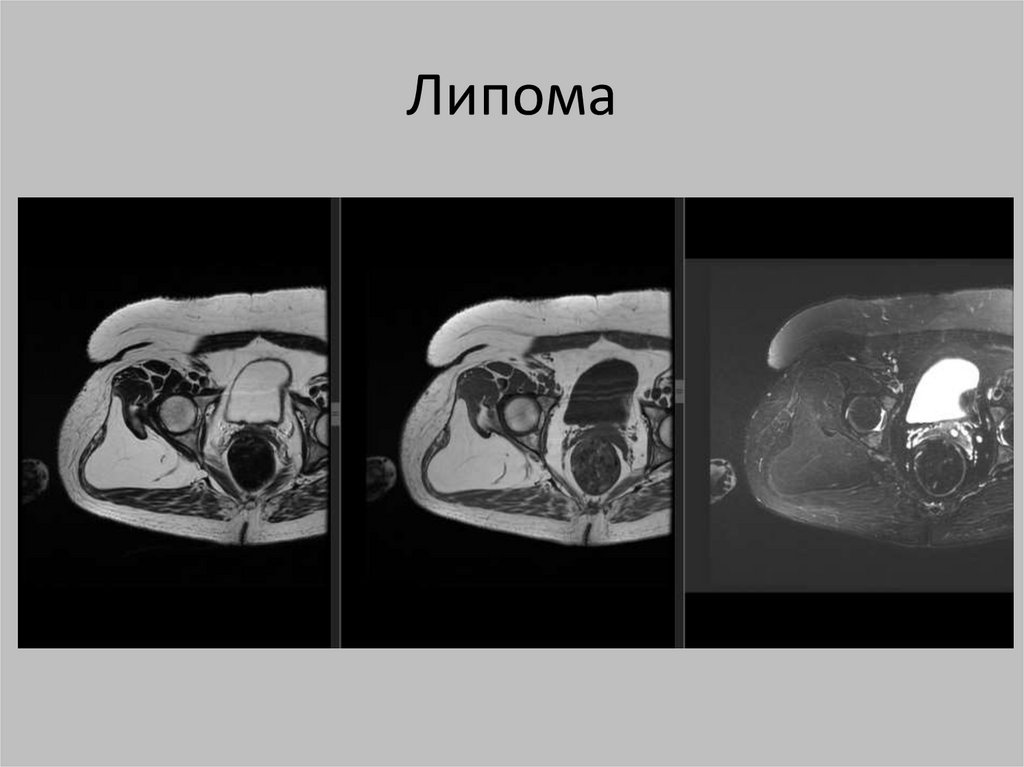

Липома